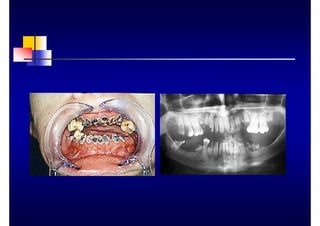

FURCACIONES

„ Grado 1: Pérdida

horizontal de los

tejidos de soporte que

no sobrepasa 1/3 del

ancho del diente

„ Grado 2: > 1/3 del

diente

„ Grado 3: La sonda

pasa de vestibular a

lingual

MOVILIDAD

„ Grado 1: 0.2-1 mm en sentido horizontal

„ Grado 2: > de 1 mm en sentido horizontal

„ Grado 3: Movilidad en el sentido axial del